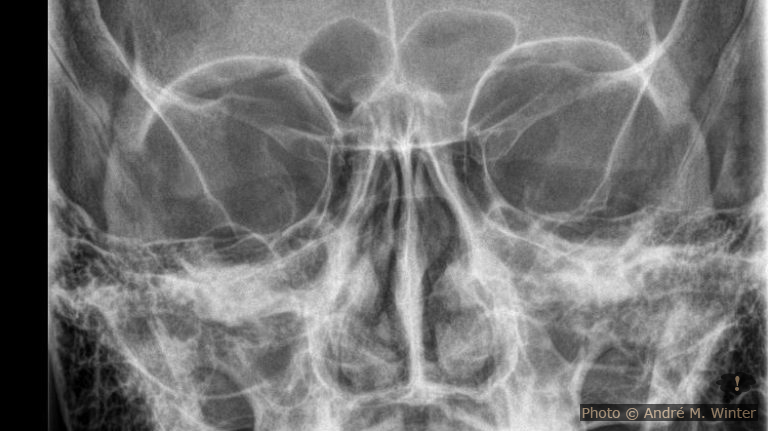

In der Nacht gehe ich vom Ehebett ins Wohnzimmer wo ich meine, den Arm besser lagern zu können. Aber an Schlafen ist nicht zu denken. Ich frühstücke, dusche noch mal und fahre Samstag den 13. Dezember 2025 mit einer Armbinde auf die Notfallambulanz. Hier fragt man mich, warum ich nicht gleich gekommen sei. Ich antworte, dass der Unfall am selben Tag passiert sei, halt kurz nach Mitternacht. Das hat jedoch nichts am später diagnostizierten Bruch geändert. In einem ersten Röntgen ist fast nichts im Ellbogen, der vorrangig schmerzt, zu erkennen. Der Aufnahmewinkel lässt anscheinend die Teile so erscheinen als wären sie gut beisammen, man sieht nur einen Schleier im Knochen. Ein zweites Röntgen bringt Klarkeit. Durch den Sturz landete das ganze Körpergewicht auf der rechten Hand. Diese hielt stand. Der Schlag setzte sich bis in den Ellbogen fort wo das sog. Radiusköpfchen brach. Der Radius ist die Speiche, also der obenliegende Knochen des Unterarms. Dieser endet im einer Hohlform die am Oberarmknochen über ein Köpfchen greift, dieses aber nicht umschliesst und bei starken Armverdrehungen sich aus “auskuppeln” kann (im Gegensatz zur besser verankerten Elle). Anscheinend war dies beim Sturz der Fall und die Halbholform traf nicht genau auf das Köpfchen gegenüber. Ein Teil der Halbholform brach aus und verschob sich über 2 Millimeter nach hinten.

Diesen Versatz sah man dann im zweiten Röntgen, welches mit 45 Grad in den Ellbogen aufgenommen wurde. Der Spalt war grösser als 2 Millimeter, aber nur knapp. Das nennt man fachlich Radiuskopffraktur rechts Mason Typ II. An dieser Grenze wird entschieden ob man eine konservative Verheilung anstrebt oder ob operiert werden muss. Über 2 Millimeter muss normalerweise operiert werden aber es gibt nur um eine par Bruchteile Millimeter darüber. In der Notfallambulanz der Klinik Innsbruck will man die Entscheidung der Handambulanz überlassen und man verpasst mir einen Spaltgips von der Hand bis zur Schulter über den Rest des Wochenendes. Der Spalt bedeutet nicht dass er abnehmbar ist, er ist bloss ein wenig leichter. Ich war ganze 6 Stunden dort. Aber auch mühsam verletzte (Schulterbruch) liess man so lange warten.